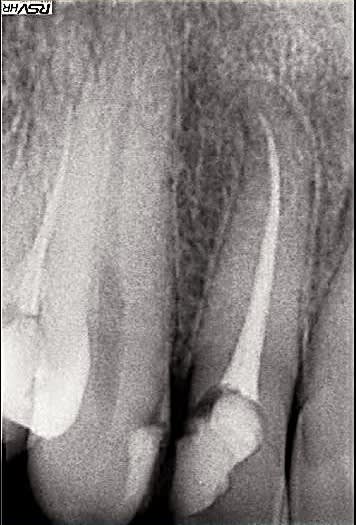

suite de la démo avec le passage d'une lésion que l'on pourrait qualifier de 4 (voire 3 si on compare avec ce que nous donne comme exemple les auteurs dans leur article) sur la radio initiale en une lésion de type 2 (en cours de cicatrisation) 3 mois après le retraitement.